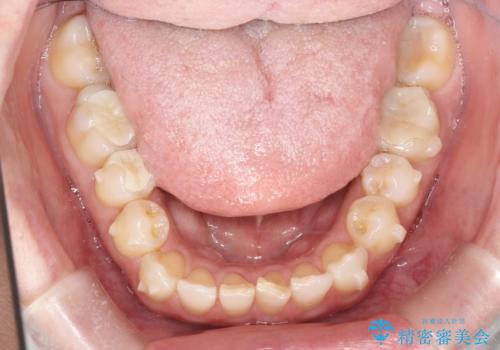

インビザラインにて治療することとしました。

内側に引っ込んでいる歯も、インビザラインにてしっかり外側に動かすことができます。